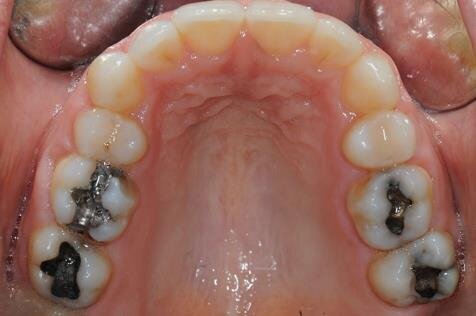

All’esame clinico del viso si osservava una sostanziale simmetria bilaterale e corrette proporzioni facciali verticali frontali e laterali (Figg. 1a-1c). Il sorriso presentava un’adeguata esposizione degli incisivi superiori e dei corridoi buccali e la centratura della linea mediana superiore rispetto al volto. All’ispezione del cavo orale, invece, si riscontrava una lieve deviazione della linea mediana inferiore verso destra di circa 1 mm, con contestuale II Classe canina a destra (Figg. 2a-2c). La mancanza del primo molare inferiore di destra aveva prodotto lo spostamento mesiale, la mesio-inclinazione del secondo e terzo molare inferiore e l’estrusione del primo molare superiore. A sinistra, invece, era riscontrabile una I Classe canina e molare. Erano presenti un moderato affollamento nell’arcata superiore ed un lieve disallineamento degli incisivi inferiori. L’overjet era lievemente aumentato e l’arcata superiore appariva lievemente contratta, soprattutto a destra. Erano presenti recessioni gengivali multiple.

Figg. 2a-2c - Foto intraorali pretrattamento: visioni frontale (a), laterali (b).